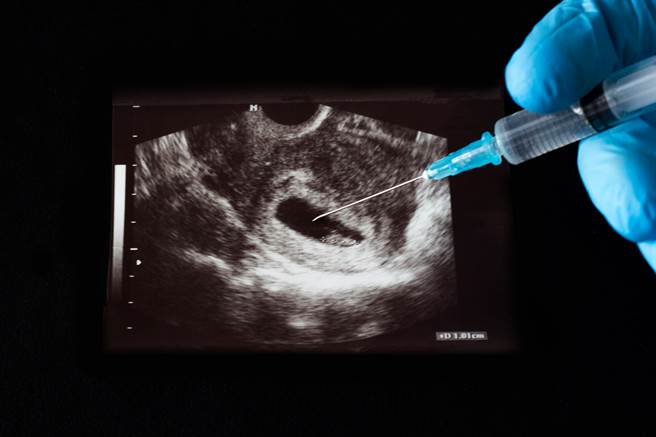

无知有多恐怖?大陆一名22岁少女日前至浙江第二医院妇产科,进行第7次人工流产,这手术对于她未来生育恐会造成影响,这让医师感到非常震惊,因此询问「为什么不避孕呢?」,没想到少女竟露出害羞表情,更回应自己不知道如何避孕,这让医师非常吃惊。

综合陆媒报导,22岁的小菲(化名)已动了7次人工流产手术,医师忧心地询问她「为什么不避孕?」,且是否知道手术对于她未来生育功能的影响,但小菲却仅回覆,「这方面的事情一直都是听男朋友的,自己也不知道怎么避孕,怀孕之后也羞于启齿告诉家长」,只能倚靠堕胎的方式解决。

由于有些地区较保守,对于性知识较不足,因此孩子若未在学校学好性知识,或对于性安全保护意识,就会造成堕胎年龄下降的状况。浙江第二医院妇产科主任郑伟对此表示,进行人工流产的患者中,又以年轻女性居多,且未婚者占一半的比例,还曾接诊到14岁的病患。

而且每到暑假期间,做人工流产的患者也跟着增加,这也显现仍有不少年轻人,对于性知识仍非常缺乏。不少网友惊讶的表示「子宫都被刮成薄膜了吧!」,还有老师提到,日前在课堂上教一年级学生性保护意识,指被衣服遮蔽的身体部位,不可随意被异性碰触,不论是爸爸或爷爷的亲人,岂料隔天就遭家长投诉,甚至痛批她不配当老师,无奈下她只能离职。